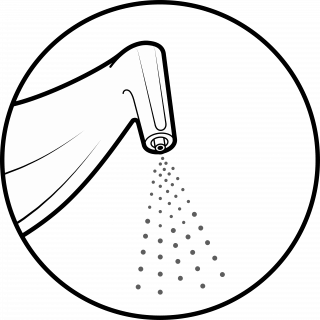

GUIDED BIOFILM THERAPY

WHAT IS GUIDED BIOFILM THERAPY?

Using the latest technologies, Biofilm Therapy is a pain-free hygiene visit that gives you a brighter, healthier smile with the highest level of comfort, safety, and efficiency.

Guided Biofilm Therapy includes Oral Hygiene Instructions with an electric toothbrush and floss, together with patient education and motivation to maintain natural teeth and implants for as long as possible.